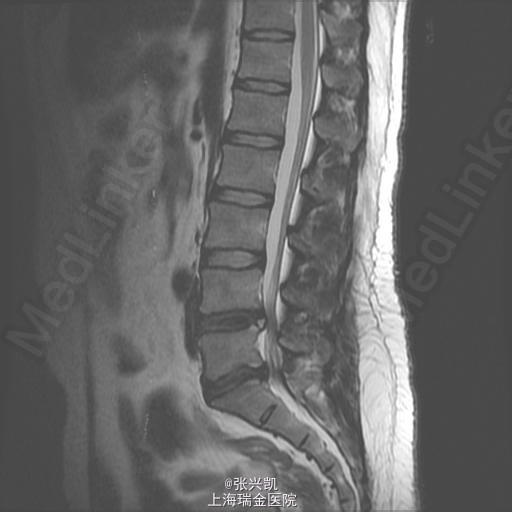

查体:脊柱无侧弯畸形,双上肢感觉活动良好,双侧股四头肌肌力正常,跟、膝腱反射(+),右腿直腿抬高试验45°,左侧70°,右侧足踝外侧麻木感 辅助检查:腰椎MR示:L4-5,L5-S1,椎间盘突出,相应节段伴狭窄,腰椎退行性改变,L5,S1相邻终板变性。

诊断: 1、腰椎椎间盘突出(L4-5,L5-S1) 2、腰椎椎管狭窄(L4-5,L5-S1) 处理: 经后路行L4-5,L5-S1椎管减压,椎间盘摘除,L4-5,L5-S1融合内固定术